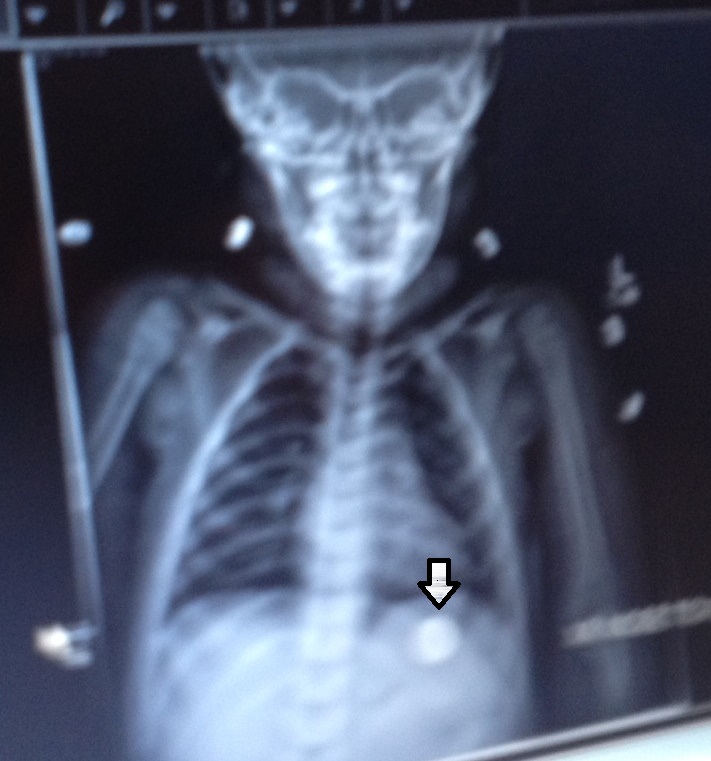

Most parenting websites will tell you it’s no big deal really (of course, like most topics they are careful what they say, they don’t want to get sued. There is always a “but” in the sentences). Kids swallow things all the time! The issue is if it makes it into the stomach or not. For my daughter, she was complaining about her chest hurting so there was a fear it was lodged someplace it wasn’t supposed to be. The pediatrician told us to take her to the hospital. Since I was already showered and dressed, it fell on me to rush her to the ER for an X-ray.

After two different nurses and an insurance worker (with paperwork to sign), my daughter was moved onto a gurney, awaiting her time to get the X-ray. We were told it could be anywhere from 20 minutes to 2 hours, because emergency cases would get preference. Since she wasn’t gagging or having trouble breathing, we were in the later category. We were put in a room in the children’s wing, and told to wait.